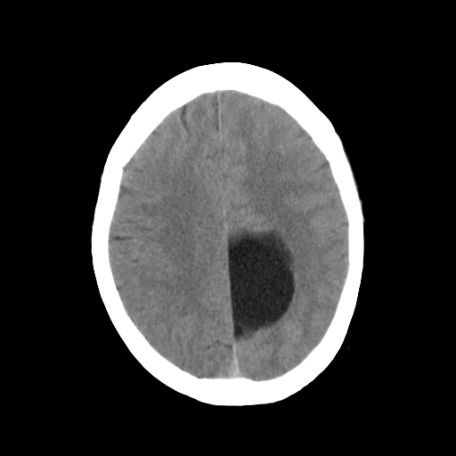

以下是引用深泽交通医院在2009-8-7 12:18:00的发言:[br]有壁结节,考虑囊变型胶质瘤

以下是引用卜一在2009-8-7 15:50:00的发言:[br]囊变性脑膜瘤!支持!

以下是引用随光逐影在2009-8-7 15:58:00的发言:[br]考虑左侧顶叶胶质瘤,不排除左侧镰旁脑膜瘤;建议行进一步检查。

以下是引用shibing在2009-8-7 16:36:00的发言:[br]增强扫描